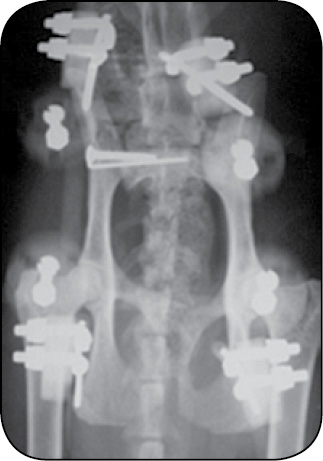

Stabilizatory można stosować w bardziej złożonych konfiguracjach w leczeniu złamań miednicy, gdyż są bardzo przydatne ze względu na problematyczną stabilizację tego obszaru. Można je również łączyć ze stabilizacją wewnętrzną, gdyż ramię dźwigni stabilizatora jest znacznie dłuższe w porównaniu do wewnętrznego implantu (płytki i wkrętu). W przypadku stabilizacji hybrydowej po kilku tygodniach, po wytworzeniu się już kalusa kostnego, stabilizator można usunąć, pozostawiając jedynie wewnętrzne implanty, gdyż będą już wtedy poddawane mniejszym obciążeniom (ryc. 20, 21).